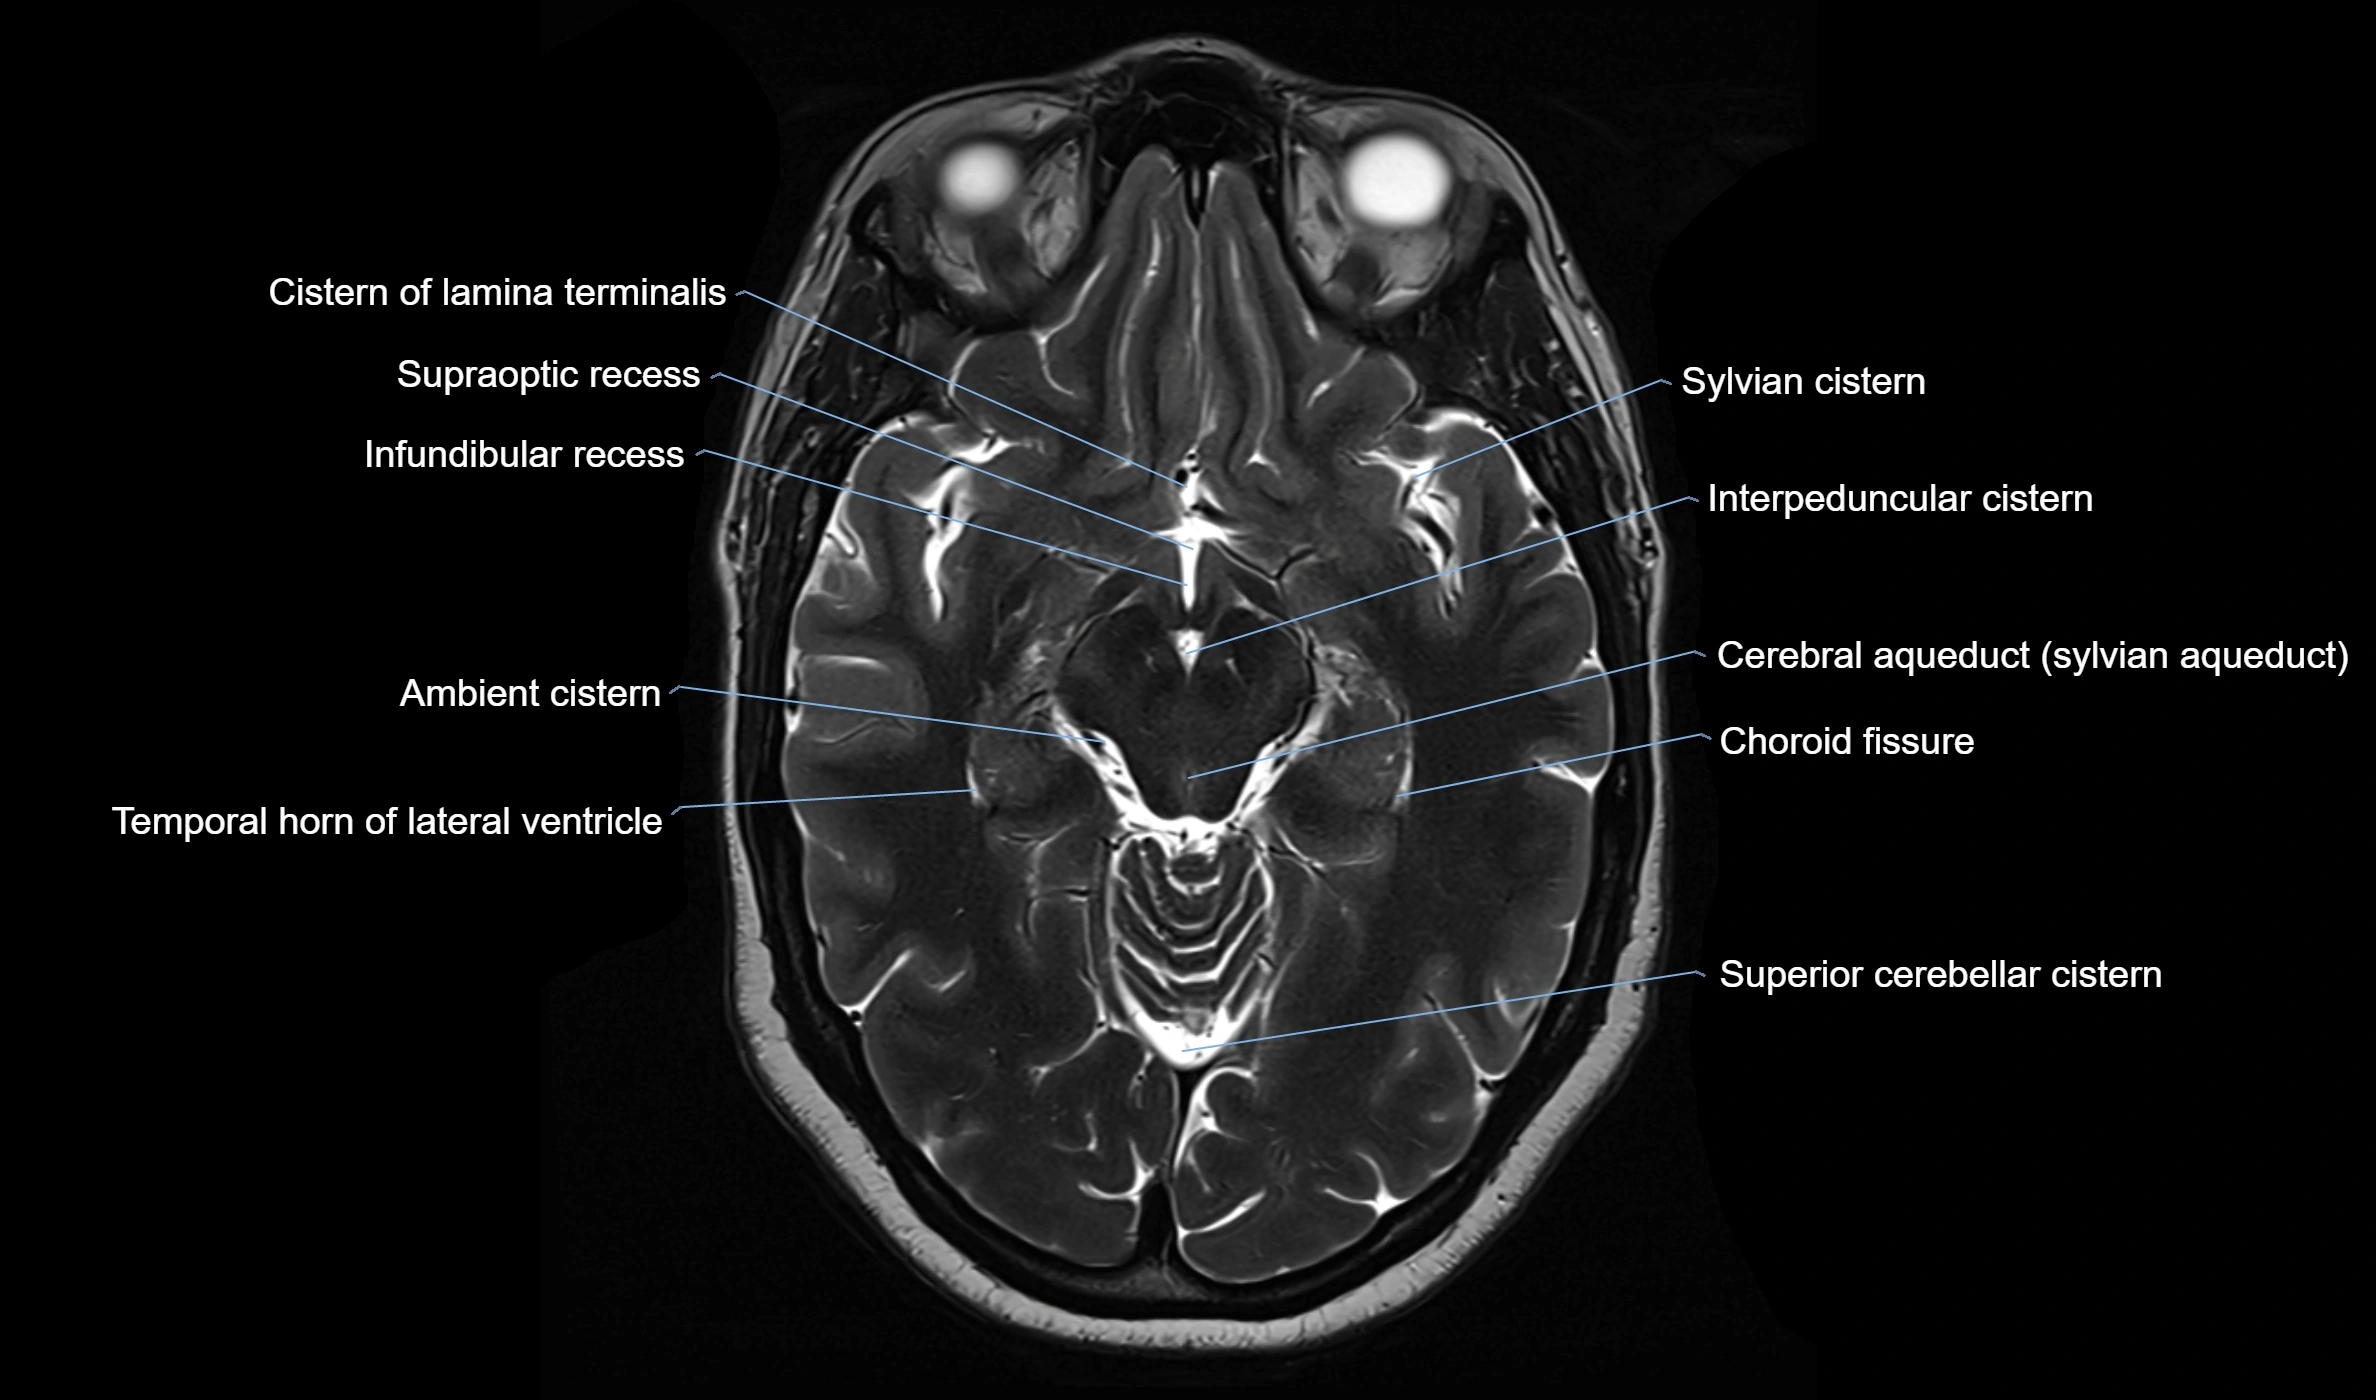

MRI images

image